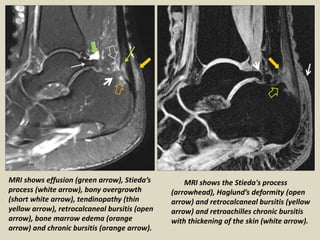

MRI shows effusion (green arrow), Stieda’s

process (white arrow), bony overgrowth

(short white arrow), tendinopathy (thin

yellow arrow), retrocalcaneal bursitis (open

arrow), bone marrow edema (orange

arrow) and chronic bursitis (orange arrow).

MRI shows the Stieda's process

(arrowhead), Haglund’s deformity (open

arrow) and retrocalcaneal bursitis (yellow

arrow) and retroachilles chronic bursitis

with thickening of the skin (white arrow).